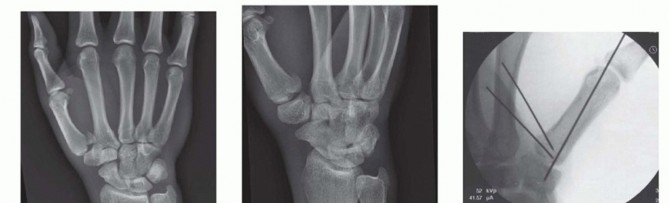

Fixation Strategies for Rolando and Comminuted Patterns

Rolando fractures present a significantly higher degree of complexity. The classical Y or T pattern often precludes simple lag screw fixation. In these instances, mini-fragment plating is the gold standard. T-plates or specialized condylar plates are contoured to fit the complex geometry of the metacarpal base. The articular fragments are first reduced and provisionally pinned, essentially converting the complex intra-articular fracture into a simpler two-part extra-articular fracture. The plate is then applied to buttress the articular fragments and bridge the metaphyseal comminution to the diaphysis.

In cases of severe, non-reconstructable articular comminution where internal fixation is impossible, joint-spanning external fixation combined with limited internal fixation (K-wires) is utilized. The external fixator relies on the principle of ligamentotaxis to restore length and align the articular fragments. Pins are placed in the trapezium (or radius) and the thumb metacarpal shaft, distracting the joint to allow for secondary bone healing while preventing collapse.